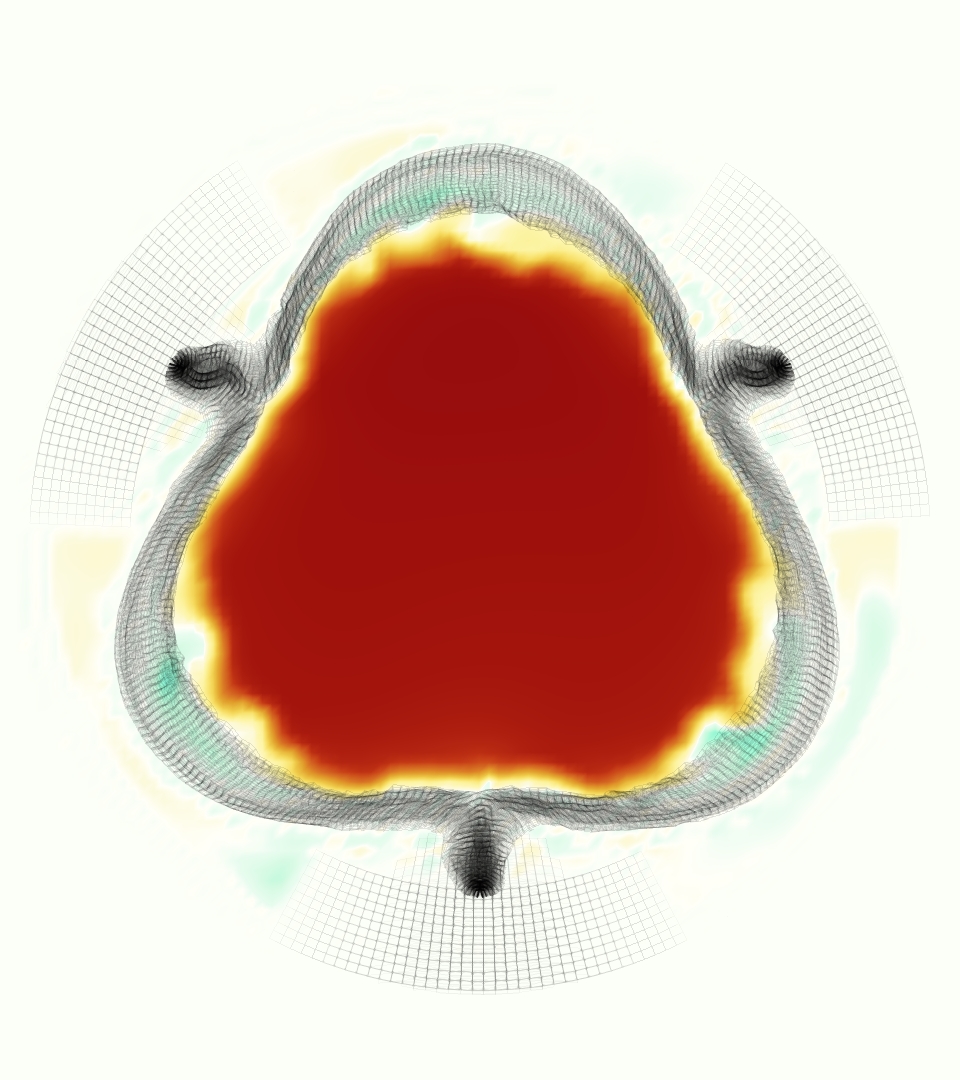

The gross morphology of the model valve that emerged from this process is shown in Figure 4. The free edge was 2.87 cm, corresponding to 3.3 cm in the predicted loaded configuration. After the pinching the leaflets together at the commissures, this left approximately 2.1 cm of free edge rest length per leaflet free to move independently of the other leaflets, within measurement error of ±0.1 cm from the free edge length of 2.2 cm measured on the prostheses. The leaflet rest height was 0.94 cm corresponding to a predicted loaded height of 1.44 cm. The measured leaflet height of 1.3 cm is nearly the predicted loaded height of 1.44 cm, which may be because the leaflets are so compliant in the radial direction, that pulling them flat to measure them achieved substantial stretches. The fiber orientation of the model runs from commissure to commissure and qualitatively matches experimental observations [38], though direct quantitative comparison is beyond the scope of this work. One minor limitation is that we do not add bending rigidity to the leaflets, beyond what emerges from the thickening process described above, and thus may not accurately capture leaflet flutter or other similar behaviors. Based on the thickness of mm, we estimated the mean tangent modulus at the predicted loaded stretches as dynes/cm2 circumferentially and dynes/cm2 radially. The prosthetic valve tissue is fixed in glutaraldehyde, and literature values for the fully-recruited circumferential tangent modulus of fixed porcine aortic valve tissue vary widely. Based on the experimental measurements of Billiar and Sacks and their constitutive law for valves fixed under 4 mmHg of pressure, we evaluated their constitutive law at the relevant stretches and and estimated the circumferential tangent modulus to be dynes/cm2 [6]. Rousseau et al. reported moduli ranging from to dynes/cm2, depending on the applied preload during fixation [36]. Sung et al. reported moduli ranging from to dynes/cm2, depending on fixation pressure [43]. Thus our estimated tangent modulus falls within the range of existing studies, so we considered our resultant modulus in good agreement given the complexity of the steps involved, phenomenological nature of the constitutive law and uncertainties in experiments. We do not have access to the precise material properties of the prosthetic valve, and further, the only literature we could find on the material properties of a similar prostheses reported the tangent modulus at one particular loading, which did not appear to be at a relevant stretch for comparisons with our model [19]. Thus, our model has material properties in a reasonable range for a fixed aortic valve prostheses (placed in the pulmonary position in our simulations), but it does not directly model the material properties of the prostheses.

We constructed the model vessel for FSI simulations from data from the MRI scans (Figure 4). The signal magnitude of 3D printed model material is distinct from the signal of the fluid in the scans, and we applied a thresholding operation to generate a three-dimensional model of the printed vessel surface. Using the MRI data ensured that the MRI and simulation coordinates were consistent in space and there were no alignment or registration errors. While using the files that generated the 3D printed model would have offered more spatial fidelity, the potential error in flow fields due to any mis-registration would have likely been much more substantial. Using Meshmixer (San Rafael, CA), we smoothed the mesh to remove stair-step effects and removed artifacts from the valve scaffold. We then remeshed to the desired edge length of 0.25 mm and extruded the model 0.25 mm and 0.5 mm to create a three-layer structure. As in the valve, this serves to eliminate the “grid aligned artifact” that can occur with pressure differences across thin membranes in the IB method [16]. Flow extenders of length 1 cm were added to the vessel at the inlet and both outlets to ensure that the normal to the vessel was aligned with the normal of the fluid box at the inlets and outlets. In FSI simulations, the vessel was held in place using target points, stiff springs of zero rest length that connect the current position of each model node to its desired position (Section 3.3). Additional linear springs are placed on each edge in the triangulated model. These springs are not meant to model a particular material and only serve to keep the vessel rigid and stationary throughout the simulation.

The emergent hemodynamics showed excellent qualitative agreement with experiments. Slice views of the axial component of fluid velocity ( component) in the sagittal plane that cuts through the center of the vessel, parallel to the flow direction, are shown in Figure 5. The flow in both the simulation and the experiment began to accelerate at the same time, with a jet forming through the open valve leaflets. The velocity, angle, and shape of the jet agreed well between the two cases during systole. The simulation captured the slight upward angle of the jet, which was not fully centered in the vessel. It also matched the location where the jet impacts the wall and the slower speed of the jet as it turns with the MPA downstream. As the flow decelerated, the fluid along the interior curve of the vessel reversed first while forward flow persisted where the jet was strongest, as seen in both the simulation and experimental results.

Slice views of the (axial) component of fluid velocity in the axial plane, orthogonal to the flow direction, show that the simulation replicated the development of the jet over the cardiac cycle. At each phase, the simulation matched the forward speed of the core of the jet and the locations of reverse flow back towards the valve annulus. While there are some differences in the shape of the jet at certain phases and locations, the simulation clearly produced the general dynamics of the cardiac cycle that are seen in the experiment.

At = 0, the axial slice directly at the valve annulus shown in columns 1 and 2 in Figure 6, there was excellent agreement between the simulation and experiment over the cardiac cycle in the speed and shape of the jet through the valve. In both cases, the axial velocity increased as the flow accelerated during systole and the valve leaflets opened, then decreased during diastole with slight negative velocity before the valve leaflets were fully closed. The forward flow through the valve annulus did not form a full circle, but rather developed a triangular shape with a point of the triangle forming along the interior curve of the vessel, at the bottom of the axial slices. At = 0, the points of this triangular jet shape aligned with the commissures of the valve. This shape persisted during peak systole and was well-matched by the simulation.

The axial slice = 0.625 cm, shown in columns 3 and 4 in Figure 6, cut through the support scaffolding of the valve and the leaflets when they are open. In the experimental data, the shape of the jet changed as it moved downstream. A triangular shape occurred, but the points were then aligned with the middle of each open leaflet as opposed to the commissures. Those points were also more rounded than they were at = 0. The peak velocity of the jet was faster at = 0.625 cm than at = 0, as the flow accelerated through the open valve leaflets. The simulation produced these features at = 0.625 cm. The triangular shape of the jet shifted similarly, and its speed increased compared to the upstream slice. As the flow decelerated into diastole, the jet shape remained roughly triangular but diminished in intensity before disappearing after valve closure.

The jet continued to develop at = 1.25 cm, an axial slice immediately downstream of the valve scaffolding and open leaflets, shown in columns 5 and 6 in Figure 6. In the experimental data, the points of the triangular jet shape extended further towards the vessel wall. In addition, regions of reversed flow developed in the locations downstream of the commissures, resulting in curved sides to the shape of the jet. Each tip of the jet was unique, due to variations in the individual leaflets in the physical bioprosthetic valve. These variations are apparent in the velocity fields, possibly because the jet edges are similar enough cycle to cycle that irregularities are still being captured even with phase averaging. Further discussion of these features can be found in Schiavone et al. [39], which showed that the jet tip shapes occurred in different pulmonary anatomies, demonstrating that they were likely due to inherent properties of each leaflet. The leaflets in the mathematical model of the valve are identical, so these nuances in leaflet variation could not be replicated. The simulation did capture some of the extension of the tips of the jet, as they were closer to vessel wall at slice = 1.25 cm than = 0.625 cm. The curves in the triangular sides of the jet were also present in the simulation, though they were less pronounced than the experimental data. At both = 0.625 cm and = 1.25 cm, the jet shape in the simulation was smoother than the jet in experiment. It is possible that the free edges of the leaflets in the mathematical model are not fully replicating the behavior of the physical leaflets of the bioprosthetic valve, in particular the amplitude or frequency of leaflet flutter, leading to the variations seen in the jet shape at = 1.25 cm downstream of the leaflet edges. The simulation, however, does capture the key features of the triangular shape and speed of the jet. Overall, qualitative comparisons demonstrated that the simulation reproduced key features of the flow during systole and diastole.